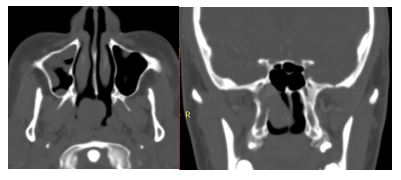

1. 04/2017. Masculino 9 años con obstrucción nasal de inicio gradual, epistaxis recurrente derecha, presentando masa en fosa nasal derecha de 3 años de evolución con extensión a seno maxilar, fosa pterigomaxilar e infratemporal derecha, así como Iisis de piso de orbita. Clasificación IIC (Radkowski) III (Chandler). Se realiza angiografía, embolización desde arteria carótida externa y se realiza resección vía Weber Ferguson, con resección completa del mismo, con buena evolución a 16 meses de posquirúrgico sin recurrencia.

1

3. 10/2017. Masculino 17 años con obstrucción nasal de inicio gradual, epistaxis recurrente derecha, masa la cavidad nasal bilateral y abombamiento de paladar blando de 4 años de evolución. TC y RM con extensión a naso y orofaringe con extensión a seno maxilar, fosa pterigomaxilar, infratemporal derecha y extensión intracraneal mínima. Clasificación IIIA (Radkowski) IV (Chandler). Se realiza angiografía, embolización de ramas de carótida externa bilateral, y resección vía endoscópica, transpalatina y Degloving, resección de 95% de tumor con tumor residual en fosa infratemporal, posterior radioterapia, con reducción gradual de tumor en los últimos 8 meses.

3

4. 03/2018. Masculino 16 años con obstrucción nasal de inicio gradual, epistaxis recurrente izquierda, masa la cavidad nasal bilateral y abombamiento de paladar blando de 3 años de evolución. TC y RM con extensión a seno maxilar izquierdo fosa infratemporal, fisura infraorbitaria e intracraneal izquierdo. Clasificación IIIA (Radkowski) IV (Chandler). Se realiza angiografía, embolización y resección vía Degloving, con resección completa de tumor, buena evolución posquirúrgica a 6 meses, sin recurrencia.

4